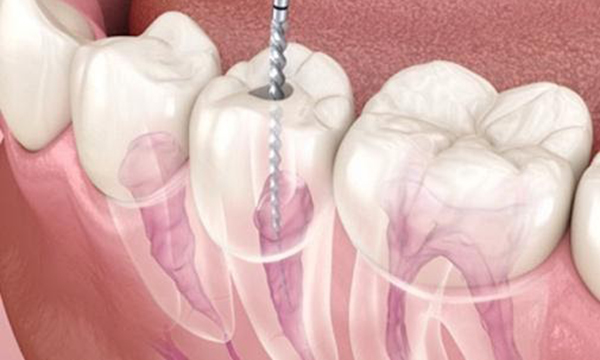

ニッケルチタンファイル

歯の神経の治療の際に、根の曲がりが強すぎると従来のステンレスの器具では根の先までのアクセスするために、歯の上部をより多く削らなければなりませんでした。

ニッケルチタンファイルを使用すると、根っこの形態が従来に比べてそのまま維持された状態で根の先にアクセスできるようになりました。

再治療の時など、根っこの形態が保存されているか否かで成功率に差が出てきます。

当院ではCTで根の状態を評価し必要に応じてニッケルチタンファイルを使用します。

ファイルの曲がり方の違い